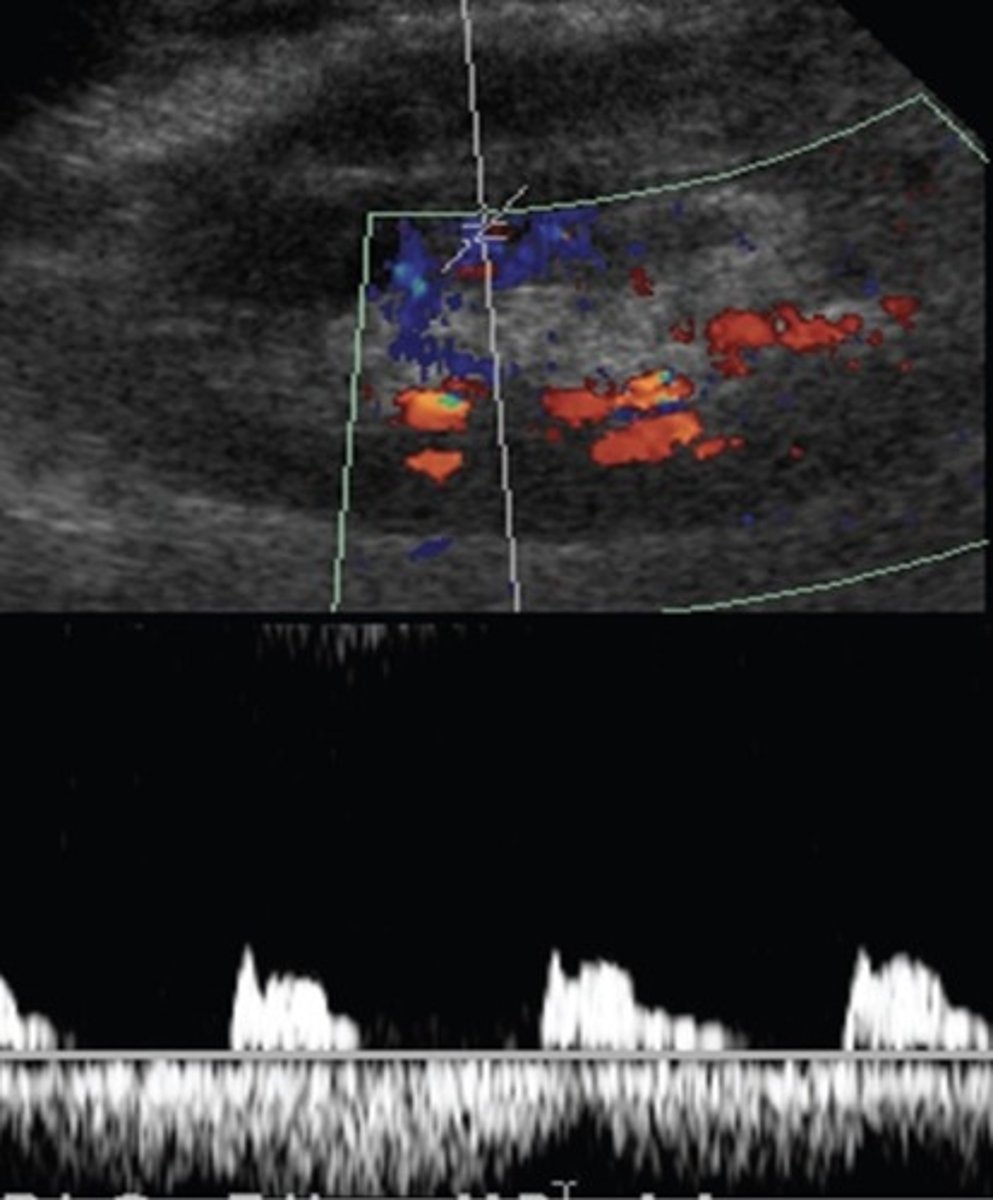

Tardus Parvus Flow

Rounded/delayed upstroke - indicates high grade stenosis proximally

100% indicative of RAS, but not always seen in RAS patients

Measured by acceleration time or acceleration index